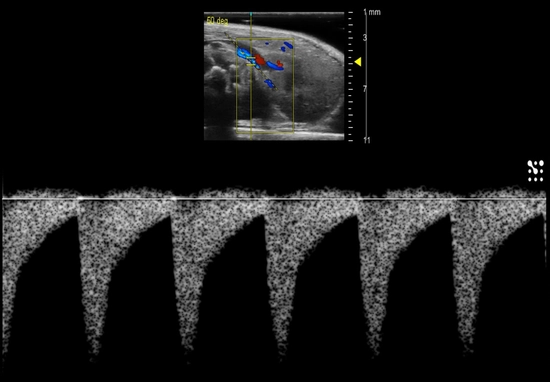

Pulsed-Wave Doppler of the renal artery in a mouse used to calculate blood flow velocities, etc.

Renal vasculature with Color Doppler in a mouse.